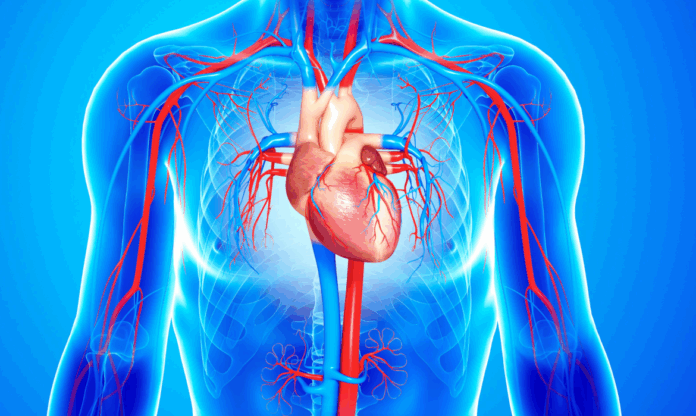

El corazón no solo late por nosotros, también depende de nuestras decisiones. De acuerdo con un artículo, la ciencia ha identificado diez hábitos fundamentales para reducir el riesgo de enfermedades cardiovasculares —la principal causa de muerte en el mundo— y fortalecer el sistema circulatorio a cualquier edad.

Los especialistas insisten en que no se trata de grandes sacrificios, sino de pequeños cambios sostenidos que pueden transformar la salud del corazón a largo plazo.

La ciencia detrás del corazón sano

Infobae destaca que los avances en cardiología preventiva confirman lo que la sabiduría popular ya intuía: la salud del corazón se construye día a día.'»

Pequeñas decisiones —desde subir escaleras hasta reducir la sal o disfrutar de una buena conversación— pueden marcar la diferencia entre una vida vulnerable y una vida plena.